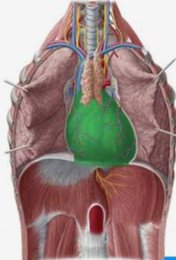

What is the Pericardium?

The fibrous sac surrounding the heart, providing protection and a barrier to infection.